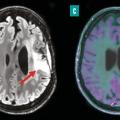

Le dépistage, le diagnostic et la prise en charge des cancers les plus fréquents, tels que le cancer du sein, de la prostate, du poumon et colo–rectal, reposent sur des avancées majeures en imagerie médicale. Grâce à des techniques performantes comme la mammographie, l’imagerie par résonance magnétique (IRM) multiparamétrique, la…

La médecine nucléaire, spécialité d’imagerie médicale en plein essor depuis cinquante ans, joue aujourd’hui un rôle important dans de nombreuses spécialités, telles que l’oncologie, la cardiologie ou encore la neurologie. Le principe de la médecine nucléaire repose sur l’utilisation de sources radioactives non scellées pour…